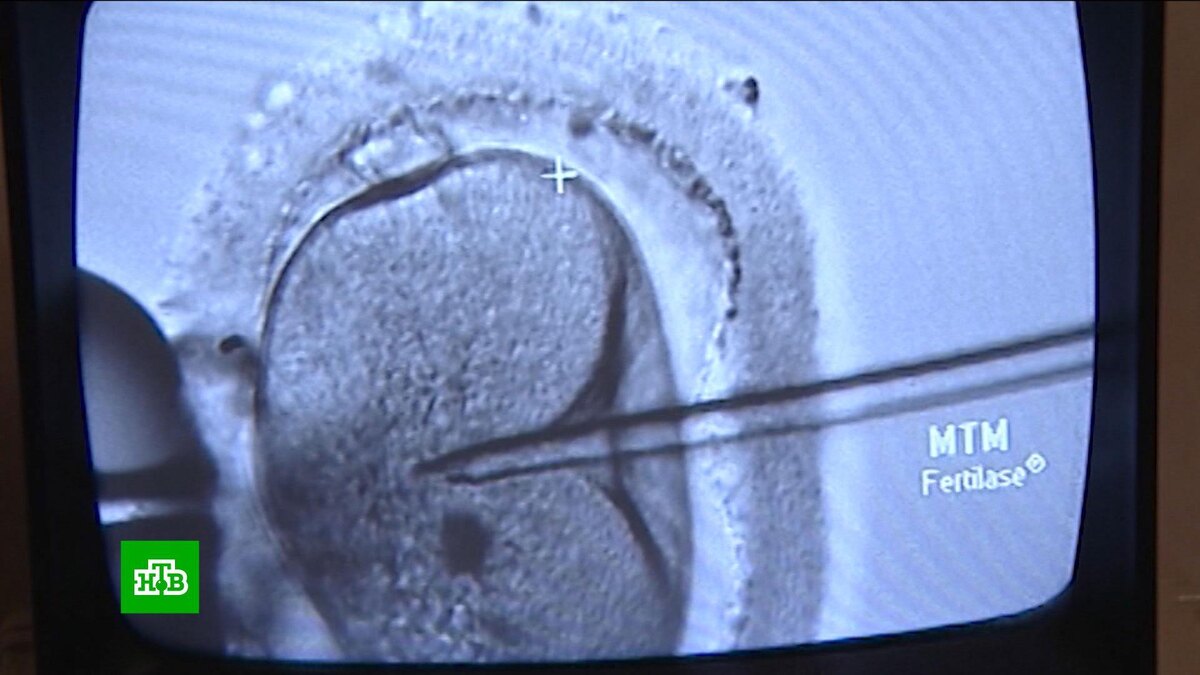

Есть тестирование еще более фантастическое. Супруги могут сдать анализы еще на стадии планирования ребенка. Чем поможет такой результат? Тем, что супруги могут воспользоваться новейшими репродуктивными технологиями — ЭКО с предимплантационной диагностикой. Проще говоря, оплодотворенные вне организма женщины эмбрионы сначала проверят на генетические патологии.

Михаил Афимов, врач, акушер-гинеколог: «Это был прорыв, конечно, в технологии ЭКО. Это метод, который позволяет оценить эмбрионы с точки зрения генетики, то есть с точки зрения их полноценности, генетического здоровья. И выбрать такие эмбрионы для переноса, что безусловно увеличивает и вероятность вынашивания беременности, и вероятность рождения здорового ребенка».